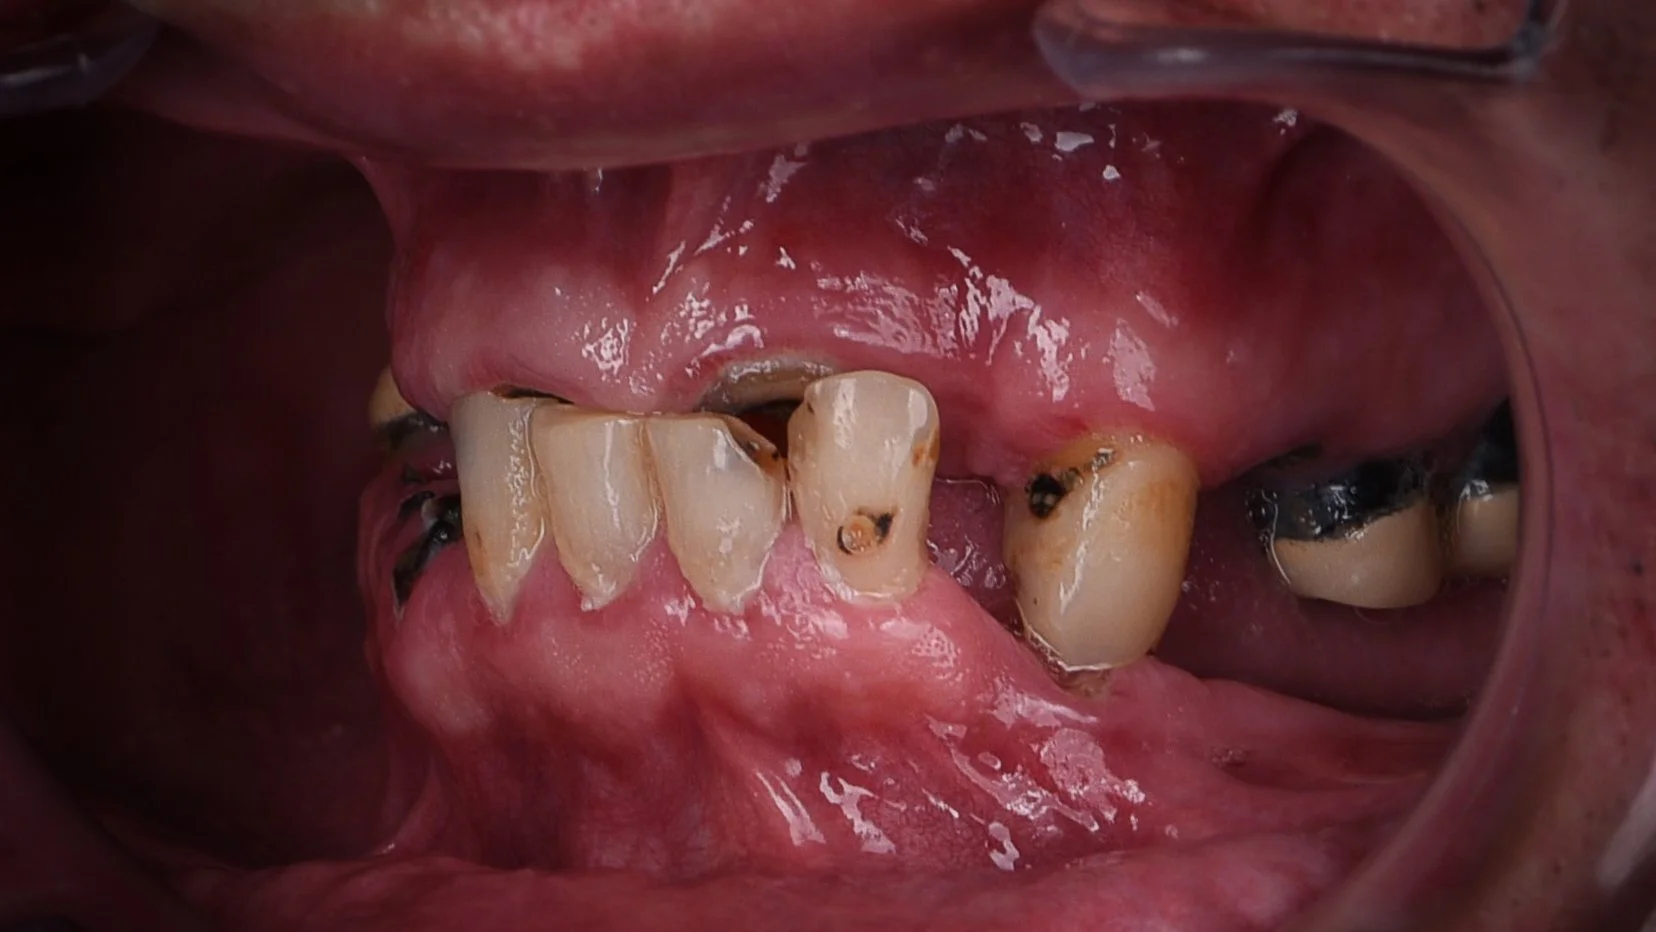

Rehabilitación completa con implates full Arch